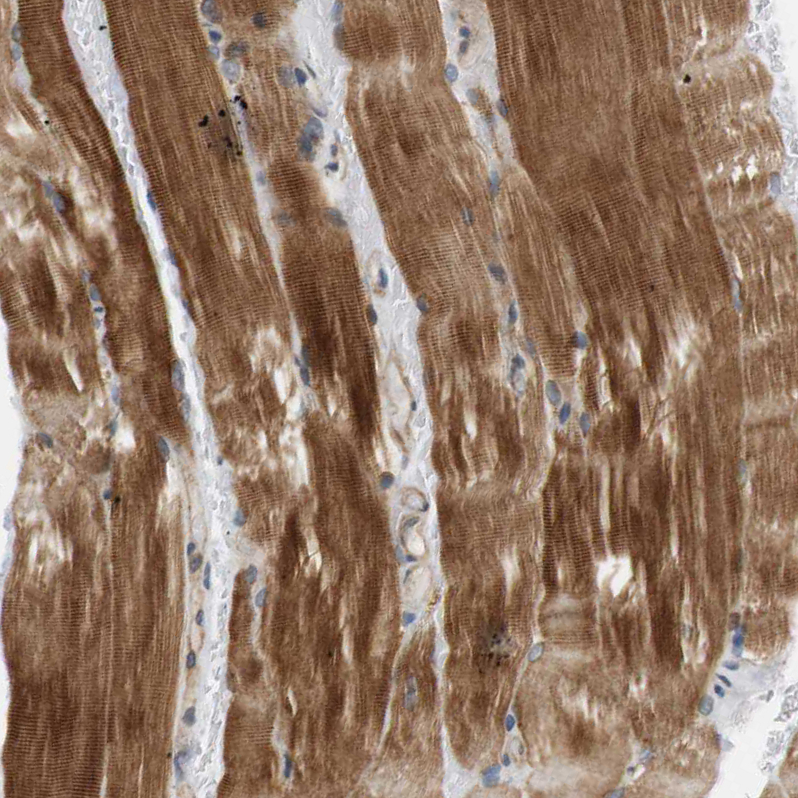

Immunohistochemical staining of human skeletal muscle shows strong cytoplasmic positivity in myocytes.